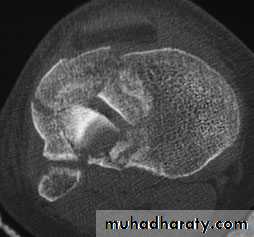

TIBIAL PLATEAU FRACTURES

Schatzker classification of Tibial Plataue Fracture

Type 1 – a vertical split of the lateral condyle.Type 2 – a vertical split of the lateral condyle combined with depression of an adjacent loadbearing part of the condyle.

Type 3 – depression of the articular surface with an intact condylar rim.

Type 4 – fracture of the medial tibial condyle.

Type 5 – fracture of both condyles.

Type 6 – combined condylar and subcondylar fractures.

Imaging

Anteroposterior, lateral and oblique x-rays will usually show the fracture, but the amount of comminution or plateau depression may not be appreciated without computer tomography (CT).Treatment